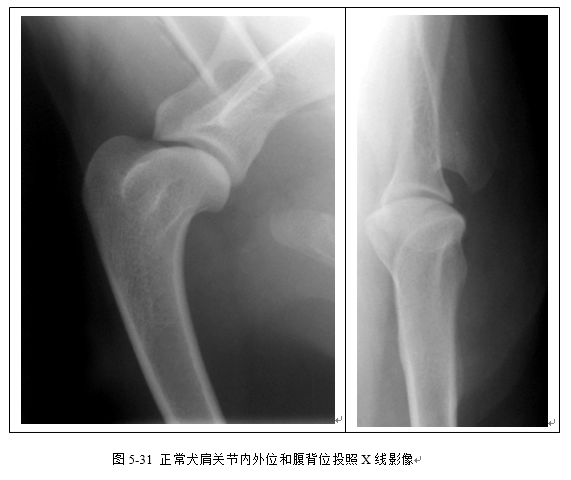

(2)识别桡尺骨、肱骨、肘关节、腕关节、肩关节X线影像(图5-28、5-29、5-30、5-31)。

二、能动关节的X线解剖

(一)关节面 X线片上表现的关节面为骨端的骨性关节面,由骨密质组成,呈一层表面光滑整齐的致密阴影。

(三)关节间隙 由于关节软骨不显影,X线片上显示的关节间隙包括大体解剖中见到的微小间隙和关节软骨。